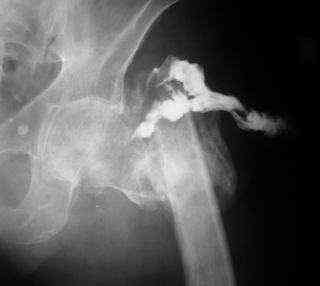

Если снимок справа по хронологии последний, то в тазобедренном сустава наступил анкилоз. Это хороший плюс костной ткани для постановки чашки эндопротеза, но отсутствие сохранения биомеханической оси бедренной кости ставит под вопрос благоприятный вариант усановки ножки эндопротеза.... Учитывая выполненную остеотомию, не считаю выполнение скелетного вытяжения лишенным смысла, для восстановления оси конечности с последующим, возможно, индивидуальным эндопротезированием.

Очень признателен Вам за ответ, но позвольте мне не согласиться с Вами. Я бы пока не делал вывод о анкилозировании тазобедренного сустава. На рентгеновских снимках, да и по данным компьютерной томографии (а этот метод один из самых современных и информативных), хорошо прослеживается постоянной ширины щель между головкой бедренной кости и вертлужной впадины. Кроме того, несложно увидеть разницу "шеечно-диафизарного угла" до и после выполнения тракции в аппарате. Хотя, Алексей, даже если я и прав, это не сильно облегчает нашу задачу.

Остеосинтез: не очень хорошо виден весь прокисмальный отломок - чем больше пенек ниже большого и малого вертелов - тем более эффективней будет интрамедуллярный остеосинтез например Y-Nail, но угол надо подобрать больше 135 гр для коррекции длины, больше угол - длиньше нога, примерно 10 гр = 1 см. Если проксимальный отломок заканчивается сразу за малым вертелом или латеральнее выше, то следует примерить пластину типа LISS or LSPDF, но лучше та, где отверстия не совмещенные, а одинарные. На операции дистальный отломок отводите под нужным углом 150 гр, к примеру, вводлите 5 винтов в проксимальный отдел = вертела и шейка, затем с торцевой компрессией фиксируете 8-и т.д. винтами диафиз к пластине. После приведения ноги - длина должна быть одинакова, сустав по-моему вполне жизнеспособен. Теперь остается тлько защититься от вторичного нагноения: был ранее в Росии Touralin - сильно помогал, ну а теперь - антибиотики - местно и в огранизм, стабильный остеосинтез, достатоточная гемоперфузия отломков. Пластического материала для осётеогенеза мне кажется там хватит, его можно измельчить и смешеть с анибиотиками - депо и того и другого. и Как говаривал Н.И. Пирогов:"операцию мы сделали, а теперь Бог вылечит!".